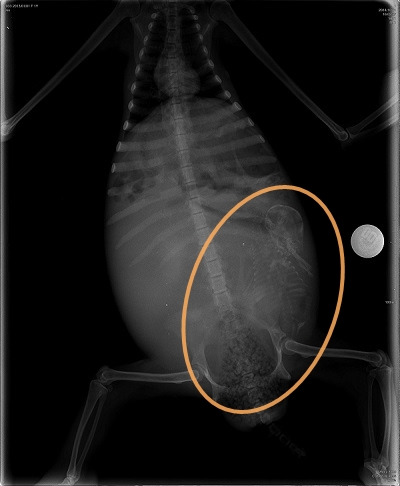

KSTR工作人員注意到樹懶有抽搐的情況,而且懷孕了。他們觀察樹懶媽媽的子宮收縮情況,但經過24小時仍沒有任何動靜,KSTR的經理Trull到動物醫院尋求幫助,才知道樹懶寶寶在媽媽體內的位置不利自然生產,Trull於是決定動刀,幫樹懶媽媽保住小孩,這是人類首次幫樹懶寶寶剖腹產。

手術非常順利,僅一個巴掌大的樹懶寶寶誕生了,牠在醫院工作人員的手上睜開眼睛,看見生命第一道風景。剪掉臍帶後,工作人員盡快清潔,並用自己的體溫幫樹懶寶寶取暖,以免失溫。